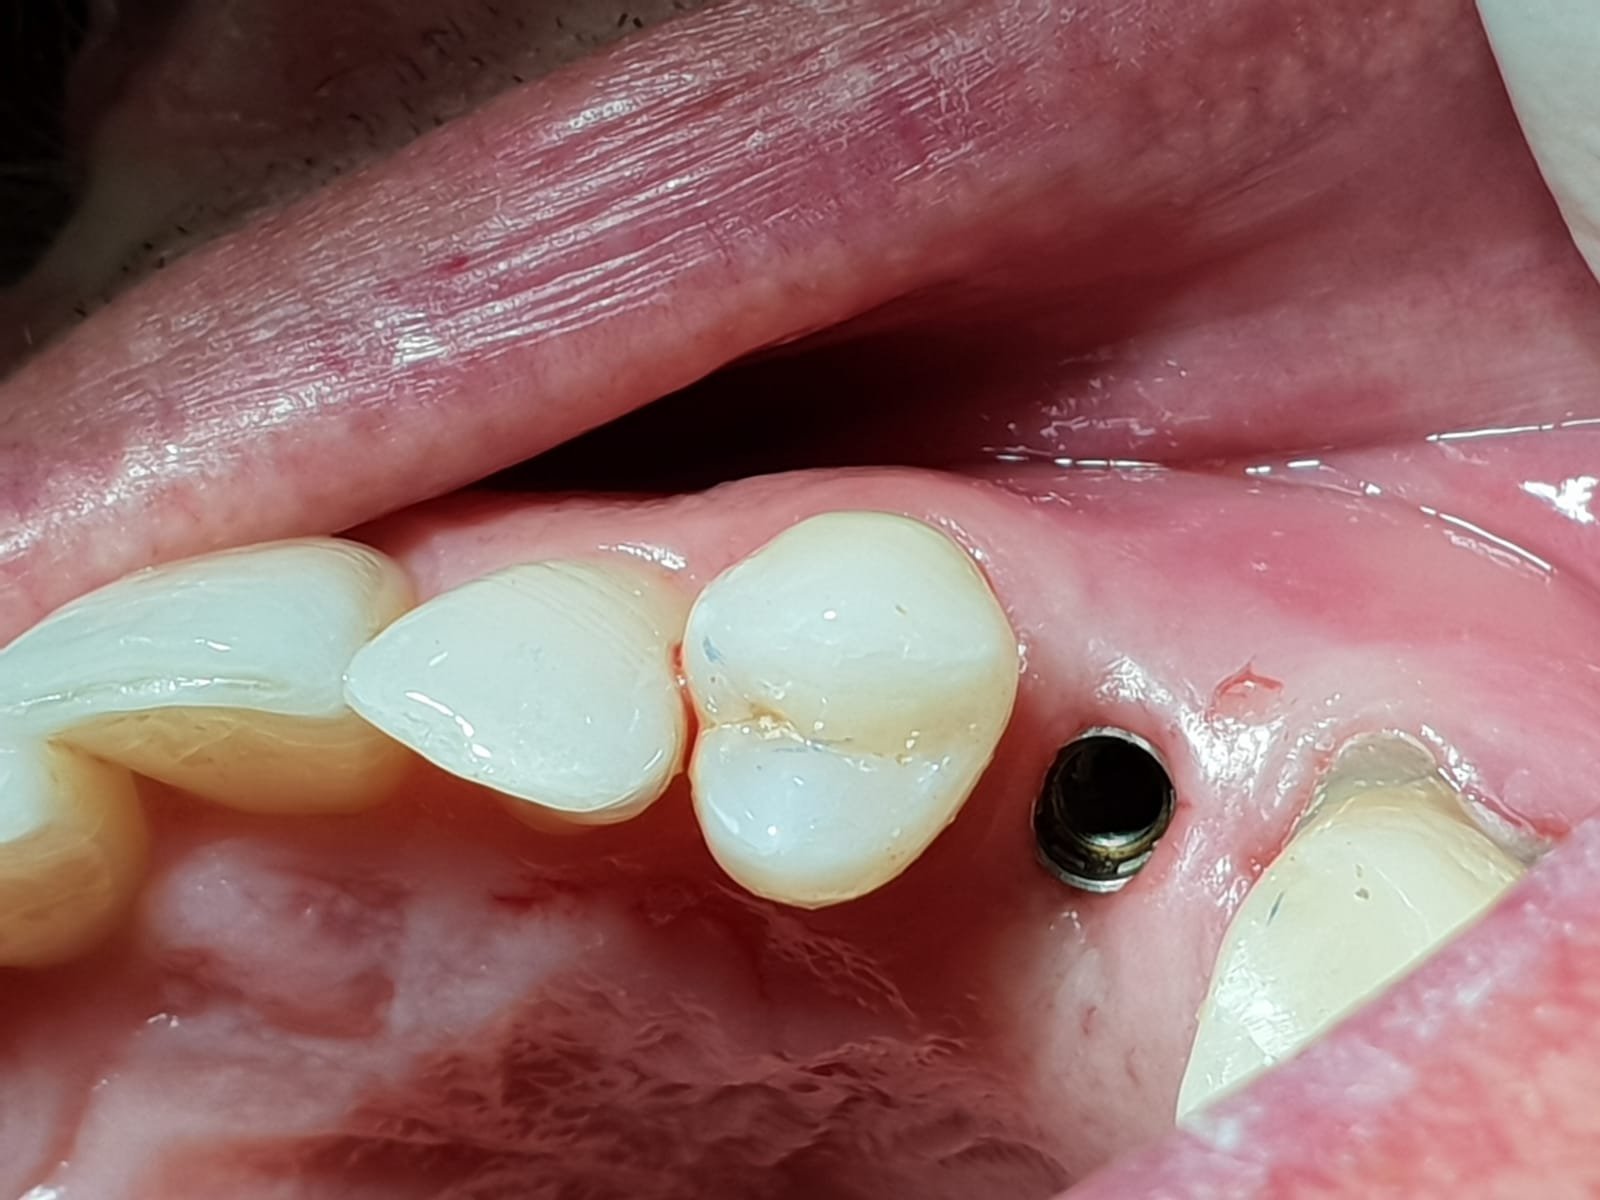

Implante colocado hace 8-11 años en Barcelona. se le cayó la corona cementada al poco de colocársela y se la cementaron de manera que no volvió a caerse hasta hace [...]